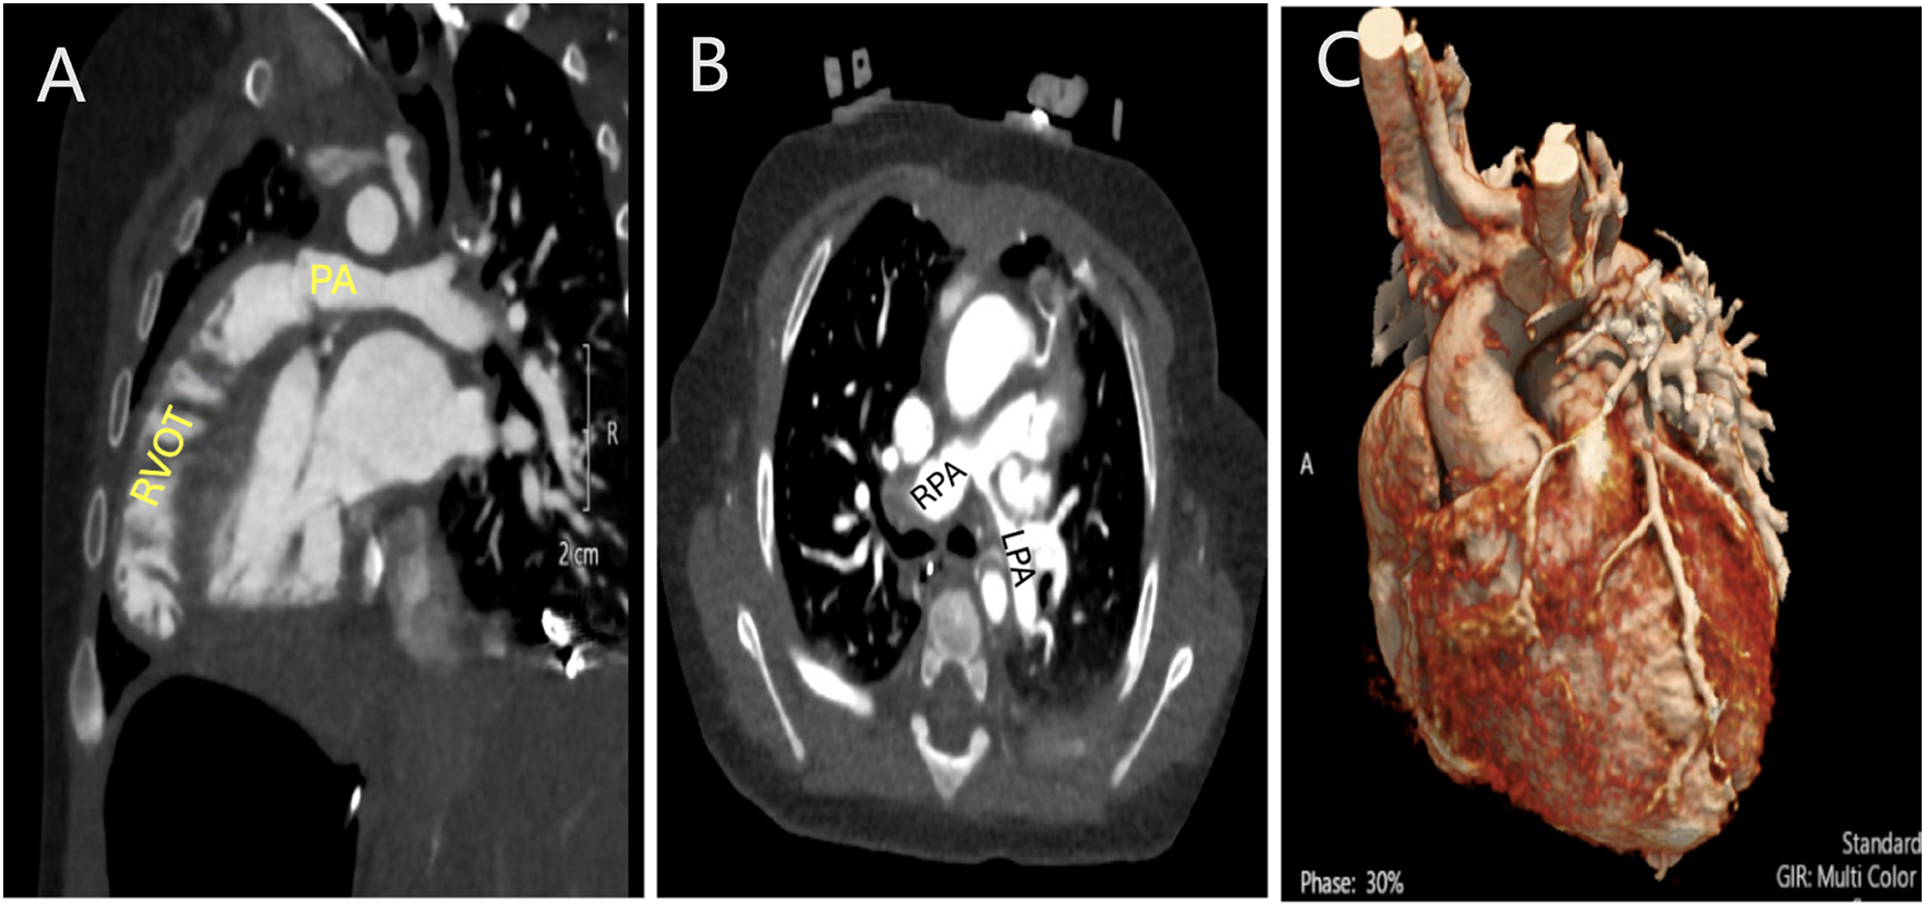

Figure 2: Computed tomography angiogram (CTA) in a patient with Tetralogy of Fallot and severe pulmonary stenosis. A: Sagittal view showing the severe sub-pulmonary right ventricular outflow tract obstruction. B: Axial view showing the branch pulmonary arteries with hypoplasia of the left pulmonary artery. C: 3D rendering demonstrating no coronary artery crossing the right ventricular outflow tract (RVOT). PA: Pulmonary artery; RPA: Right pulmonary artery. LPA: Left pulmonary artery